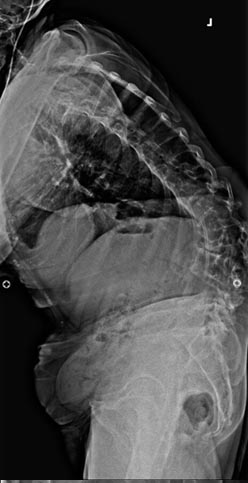

58 year old presenting with low back pain and bilateral leg pain especially when he stands for a few minutes or walks more than a few blocks.

Solid fusion 2 years postop